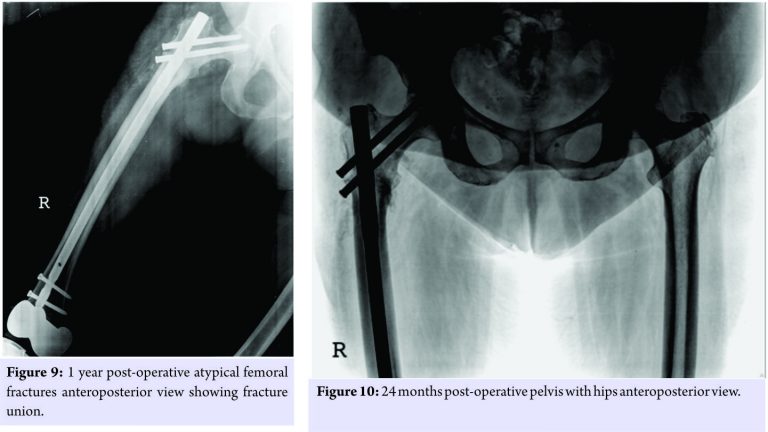

The knee replacement was unrelated to the sub-trochanteric fracture. For the subtrochanteric fracture of femur, regular follow-ups were done postoperatively with serial X-rays. Blood investigations were done, and serum calcium was 9.5mg/dl, and serum Vitamin D3 was 20ng/ml which was optimized with 6,00,000 IU of intramuscular Vitamin D3 and maintained by oral Vitamin D3 medications. At 3 months, the fracture was in delayed union (Fig. 5),and hence, the patient was started on injection Teriparatide 20mcg subcutaneous for a period of 18 months. The patient was kept non-weight bearing. The 6 months X-ray showed further progression in fracture healing (Fig. 6),and the patient was allowed partial weight bearing. In October 2013, 10 months after stopping Alendronate, she again came with the complaint of pain in the right side of the jaw; X-rays showed relapse of ONJ (Fig. 7) sequestrectomy was done on the right mandible. In February 2014, 13 months after stopping Alendronate, the patient came with the increased pain of the right mandible and was diagnosed as a fracture of the right mandible; the fracture was operated on and fixed with a plate in February 2014 (Fig.8).

Meanwhile, the patient continued injection Teriparatide. At 1year postoperatively, the atypical femoral subtrochanteric fracture had healed (Fig. 9) and the patient was allowed full weight bearing. 24 months postoperatively, X-rays confirmed solid union of the atypical subtrochanteric femoral fracture (Fig.10). On recent review, the patient walks full weight bearing without the need of any support, with a normal gait and is completely asymptomatic as regards the femur as well as the jaw.